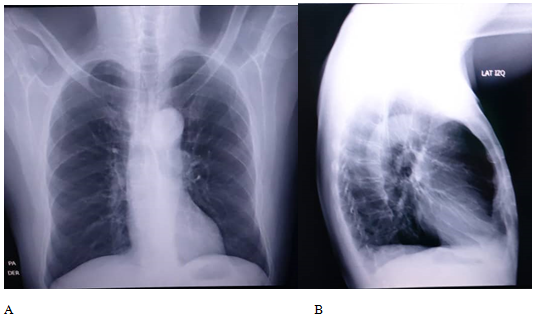

A needle biopsy (trucut) and culture of the sample is performed on the 11-18-2020, with results showing chronic granulomatous inflammation with multinucleated giant cells, focus of necrosis, an inflammation, probably due to infection, no discarding bony tuberculosis. On 12-07-2020, a positive response to PPD test (18 mm) is reported, and besides that the culture reports positive for Staphylococcus aureus, being diagnosed as: Bony tuberculosis of the left calcaneus bone, superinfected. Lab tests are performed not showing alterations, and on the chest, x-rays taken on 01-18-2021 depicted left pleural effusion without any respiratory symptoms.

The image studies performed in a serial way, allow to observe the osteolytic process and the inflammatory response seen in those chronic cases. MRI, is especially useful in evaluating soft tissues, and the computed tomography, very much useful in evaluating bone destruction, worked together in these cases. It should be advice, the use of the bone scan, or PET-CT or virtual-PET, to discard polyarticular affectation. This entity is very often confused with other pathologies. Differential diagnosis has to be made with osteomyelitis, Paget’s disease, sarcomas and other pseudo tumoral lesions, which usually are the initial diagnosis, and TBC is a discard diagnosis. The adequate diagnosis is made late because of lack of pathognomonic findings (Figure 1 - 4).10

Figure 1 Thorax AP and Lateral.